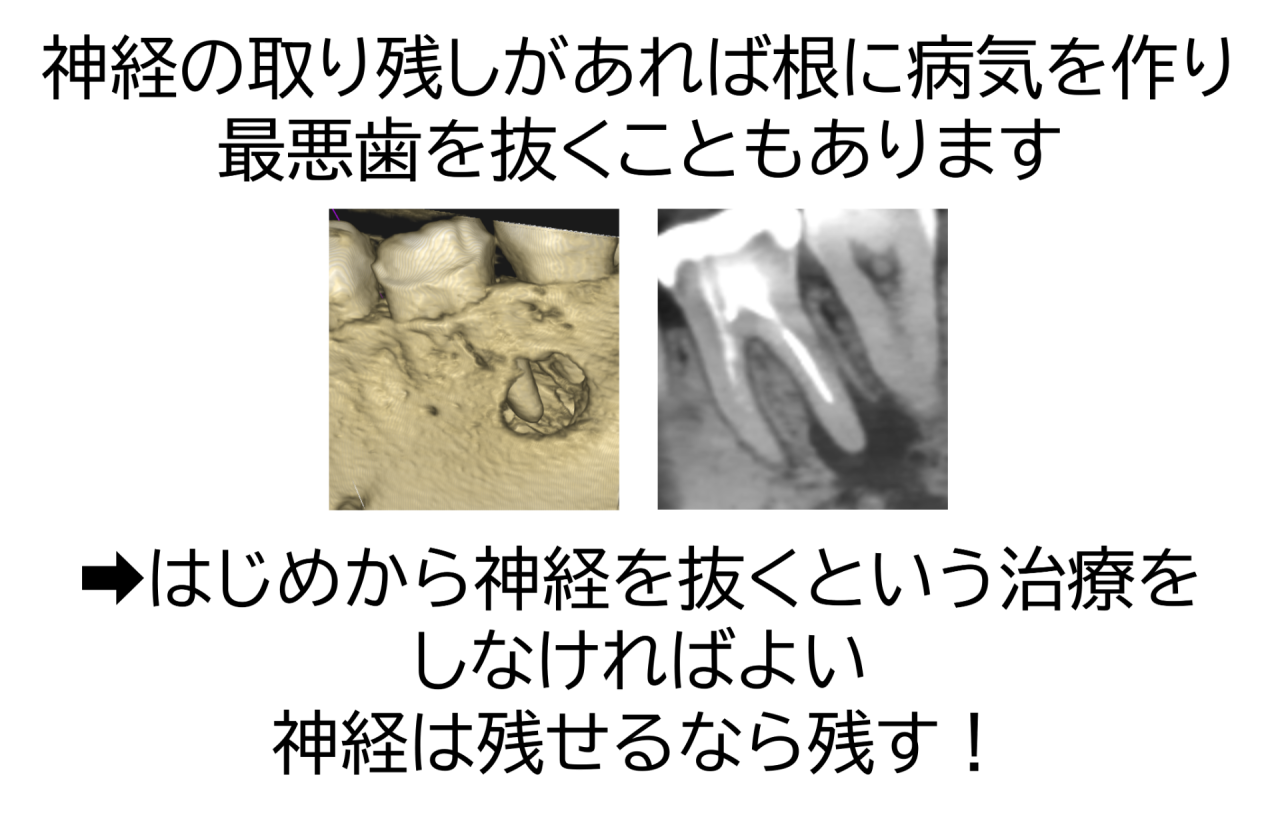

神経を抜く処置は非常に繊細で難しく、神経は細く複雑に入り組んでいるため、きれいにするには高い精度が求められます。

精度が低く神経の取り残しなどが起きれば、処置後に再感染や根の先の病気など、将来的なトラブルが起こる可能性があります。最悪歯を抜くこともあります。できることなら神経は抜かない方が絶対に良いのです。

つまり、神経を取るのは最後の手段と考え、早期発見・早期治療によって神経を守ることが大切です。「少ししみる」「噛むと違和感がある」といった初期のサインがあれば、すぐに歯科を受診しましょう。